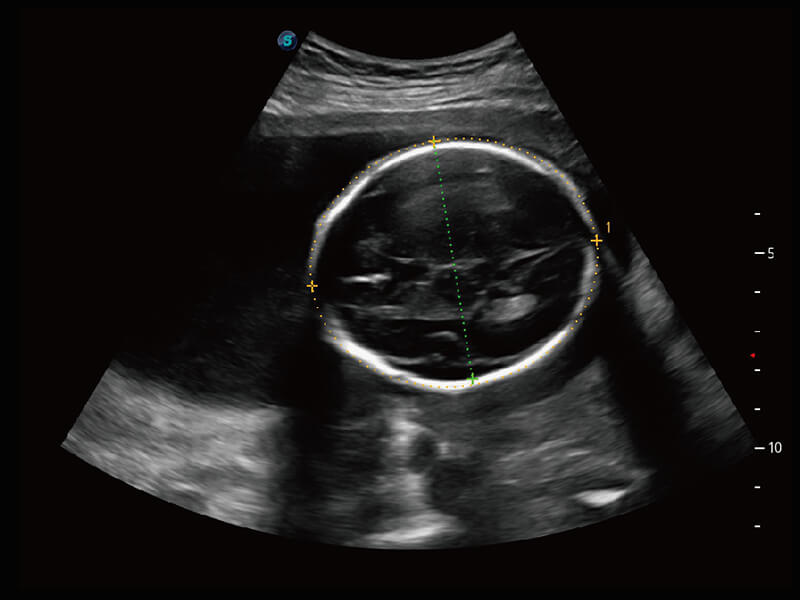

S60探头工艺,从前端信号处理每一个环节采集无损声学数据,真实还原组织原貌,再现解剖细节。

• 腹部单晶体探头( C1-6A )

• 新型复合材料探头( 12L-A )

• 高分辨率容积探头( VC2-9A )